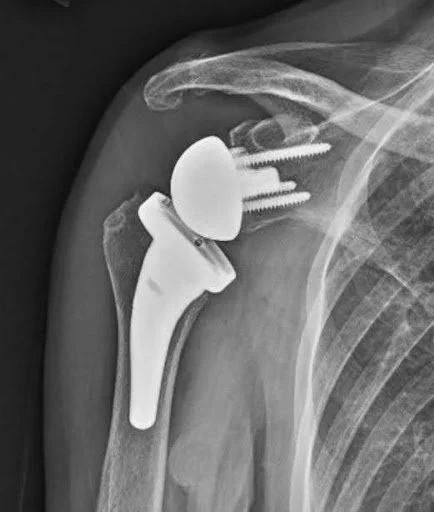

Total Shoulder X-Ray (Stem + Stemless)

Total shoulder x-ray.

Total Shoulder Arthroplasty: An anatomic total shoulder replacement recreates the normal anatomy of the shoulder. The humeral head (ball) is removed and replaced with a metal ball connected to a short stem (made of titanium and cobalt chrome alloys). The glenoid (the socket) is smoothed and a smooth shallow plastic cup (made from polyethylene) is securely affixed with bone cement.

The most common reason for performing a total shoulder arthroplasty is severe shoulder osteoarthritis with a healthy rotator cuff.